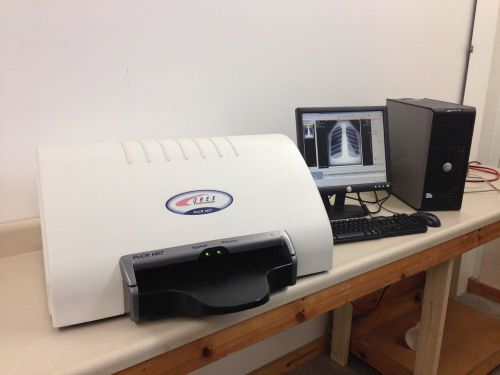

Orex ACL4 - Complete working CR System